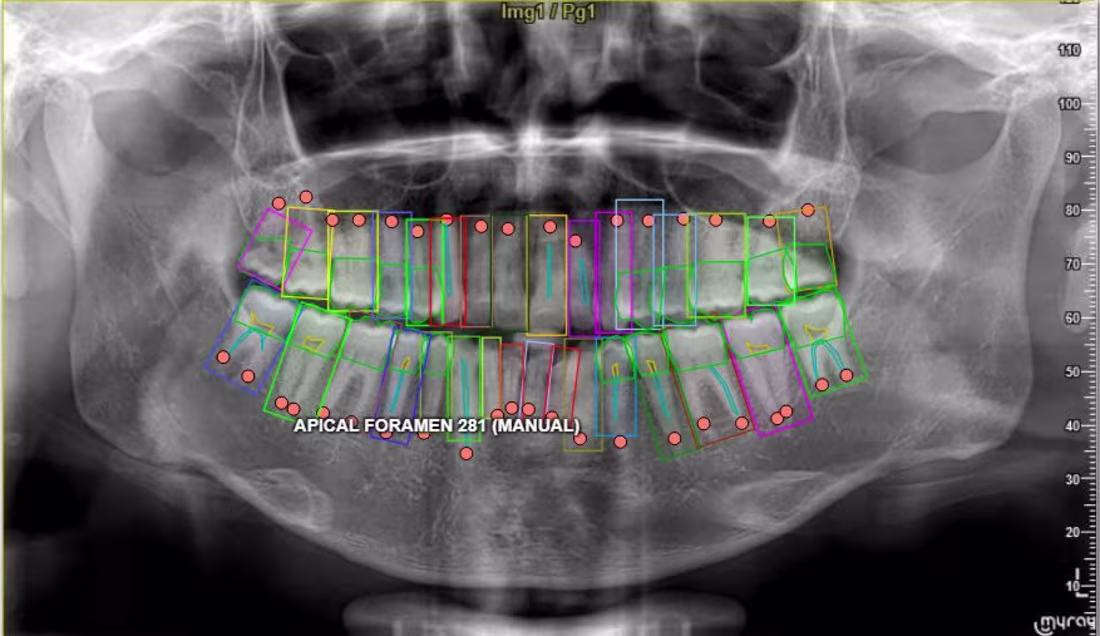

Cover image for Annotated complex dental X-ray medical

Annotated complex dental X-ray medical imaging datasets used to train AI models for healthcare applications. The project involved precise labeling of anatomical structures including teeth boundaries, roots, and surrounding regions using polygon and keypoint annotation techniques. The objective was to generate high-quality training datasets that allow machine learning systems to accurately detect dental structures and support medical imaging analysis. Responsibilities included: • Image segmentation and polygon annotation • Keypoint labeling for anatomical structures • Dataset preparation for machine learning models • Annotation quality control and validation This work contributes to the development of AI systems used in medical diagnostics and healthcare imaging analysis.